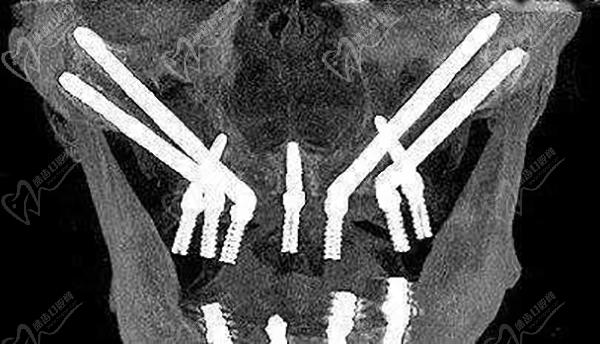

上海鼎植永博口腔的種植牙技術(shù)非常先進(jìn),走在種植牙領(lǐng)域的前沿,它家獨(dú)研的專li技術(shù)VIIV穿顴穿翼種植技術(shù)堪稱種植手術(shù)的“珠穆朗瑪”,對(duì)于牙槽骨重度萎縮、全口無(wú)牙頜患者也能輕松快捷進(jìn)行全口種植牙,而不再是被種植牙拒之門(mén)外了,也不用進(jìn)行繁瑣的植骨種植,省時(shí)省力!

局麻下改良頜外顴骨種植技術(shù)

高振華醫(yī)生對(duì)于全口、半口即刻種植、即刻修復(fù),復(fù)雜種植病例有著較深的研究,至今已完成超3000例全牙列重度缺失缺損穿顴穿翼VIIV缺骨種植即刻修復(fù)手術(shù),有著非常長(zhǎng)期穩(wěn)定的治療成效,患者口碑特別好,受到了眾多贊譽(yù)!